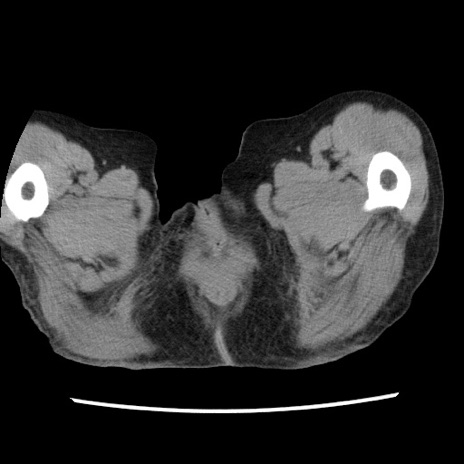

症例1(横断像)

症例

【症例】80歳代女性

【主訴】腹痛

【現病歴】8時間前から腹痛あり来院。

【既往歴】糖尿病、脂質異常症、子宮体癌にて子宮全摘術

【身体所見】意識清明・会話良好だが腹痛で苦悶様、全腹部にわたって反跳痛と圧痛あり

【データ】WBC 13600、CRP 0.14、LDH 224、CK 90